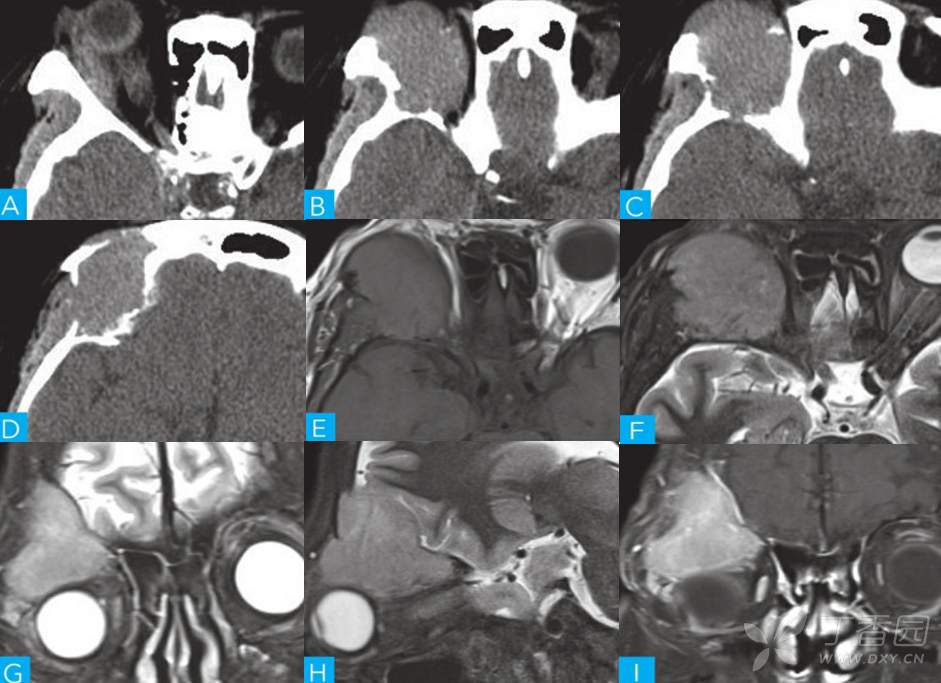

【影像诊断与鉴别011】渐进性右眼突出伴双眼视物黑影半年余~⟬回帖即可显示答案⟭

主诉:渐进性右眼突出伴双眼视物黑影半年余。

简要病史:半年前无明显诱因逐渐出现右侧眼球突出、 眼角歪斜、 伴双眼视物黑影。 就诊于当地医院眼科, 行右侧眼部息肉切除术(具体不详) , 后眼球突出未见明显好转就诊于眼科。 病人起病以来精神、 饮食睡眠可, 二便及体重体力未见明显变化。

体格检查:右侧眼角歪斜, 双瞳孔等大, 直径3mm, 对光反射灵敏, 视力L/R: 1.0/0.6。

实验室检查: 红细胞计数 3.48×1012/L(3.8~5.1) 、 血红蛋白107g/L(115~150) 、 血细胞比容 30.3%(35~45) 。 天冬氨酸氨基转移酶 40U/L(4~32) 、 总蛋白 59g/L(64~83) 、 白蛋白 25.5g/L(35~52) 、 尿素1.25mmol/L(1.7~8.3) 、 eGFR69.4ml/min/1.73m2(>90) 、 钙 1.99mmol/L(2.15~2.55) 。